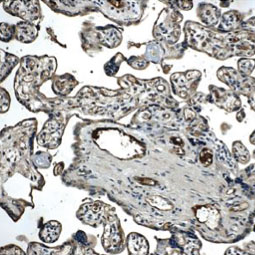

![TIE1 antibody [12D9] (GTX52470)](/upload/media/research/Cancer/Angiogenesis/5.jpg)